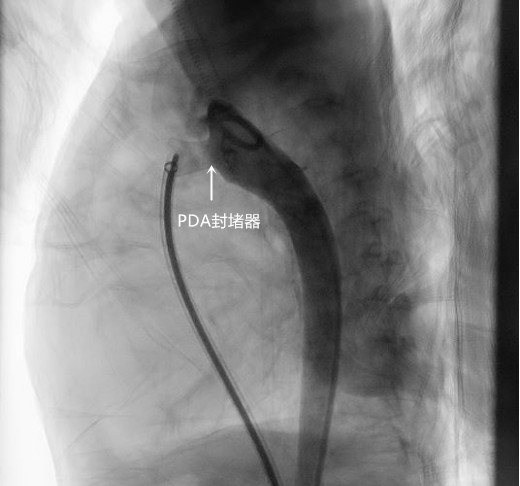

儿童心血管专科负责人刘丽萍副主任医师团队联合心脏大血管外科主任周文武教授团队再次对希希进行评估,通过检查发现外院多次提示的主动脉缩窄是继发“动脉导管未闭”所致。如果PDA能够通过介入封堵治疗,那么术后感染、心衰、休克、呼吸机相关肺炎等相关风险就大大减少,也可达到家属所期望的“无瘢痕、少创伤”。现在的希希营养不良严重、体重轻、有肺动脉高压、心功能没有完全恢复,介入风险极高,手术难度大。跟家属深入沟通后,团队邀请麻醉科一起,再次梳理了整个病程,做好了相关可能出现问题的所有应对准备。

最终,刘丽萍副主任医师、刘震宇副主任医师克服重重困难为希希完成了这场艰难的手术,历时1.5小时。术后孩子生命体征平稳,直接回到病房术后观察。

手术第二天,希希父母开心的表示,从来都没有看见希希睡得这么安稳,以前用手放在胸口都可以感觉到的心脏杂音不见了,且手术穿刺点仅3mm,结痂脱落后几乎无疤痕。4天后希希顺利出院了。